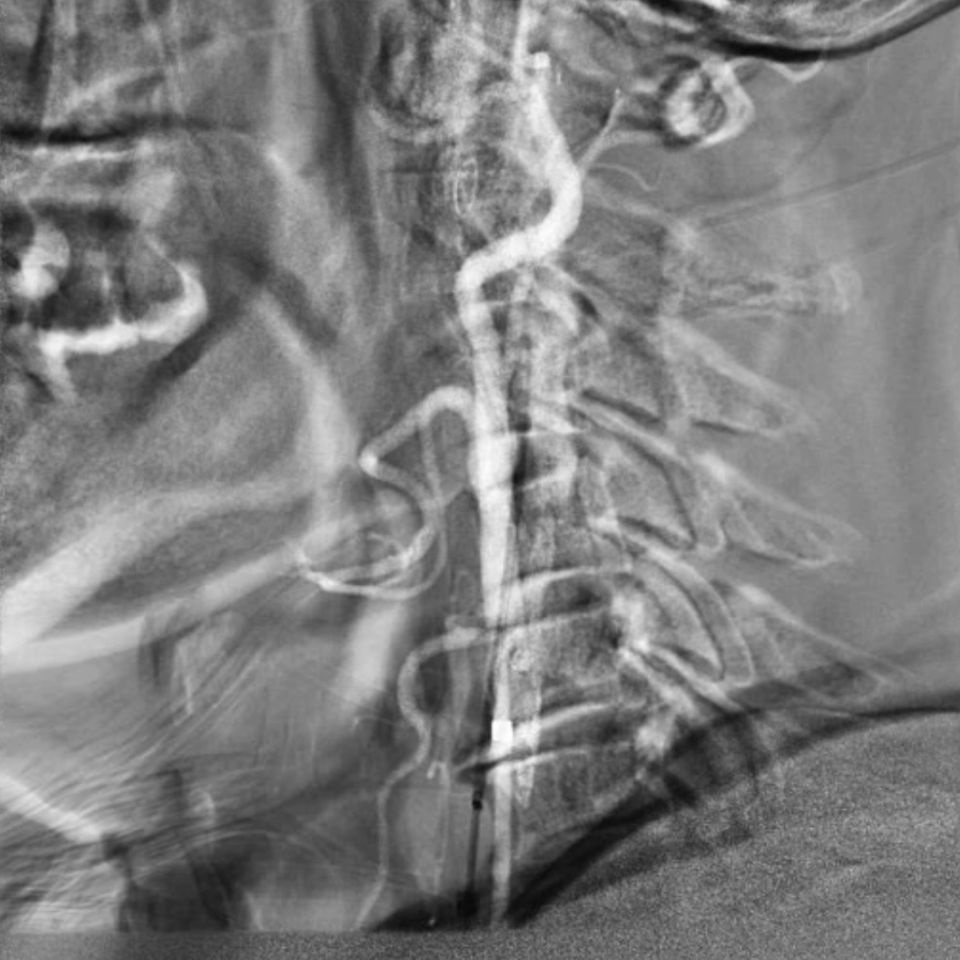

通路建立:精准操作减少血管损伤

穿刺与鞘管置入:局麻下穿刺右侧桡动脉,置入6F动脉鞘;

导管塑形与定位:使用SIMMONS导管选择左侧颈总动脉,操作时需轻柔(避免导管头端触碰血管壁导致斑块脱落),通过“反八字”塑形可精准对接左侧颈总动脉,导管弯部挂于颈动脉分叉处提供稳定支撑;

长鞘置入:在左前斜位透视下送入90cm长鞘,全程观察方向以避免阻力过大导致血管损伤

脑保护:Filterwire保护伞的规范使用

选用伞与导丝一体的Filterwire保护伞(on-wire设计),操作要点:导丝尖端柔软,轻松通过狭窄病变;在远端颈内动脉平直段释放保护伞,确保完全贴壁,有效拦截术中脱落的斑块。